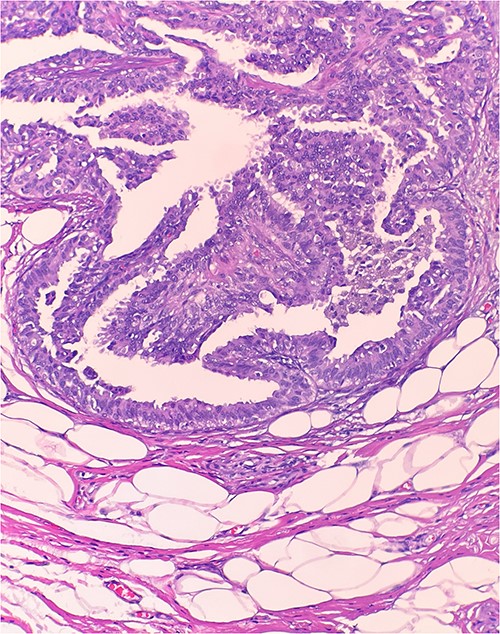

This is a 50-year-old female with a history of bilateral lumpectomy who presented for a left axillary mass evaluation. The patient underwent a bilateral lumpectomy in 2010 for bilateral IDP. Patient’s maternal cousin passed away from breast cancer. During the axillary mass work up, a 3 cm non-tender and mobile mass was noted. Mammogram showed a 2.6 cm micro-lobulated mass with solid and cystic components in the left axillary region. Ultrasound guided core needle biopsy was subsequently performed. Microscopic examination revealed arborizing fibrovascular cores lined by outer layer of luminal cells and an inner layer of myoepithelial cells (Fig. 1). Other area also showed focal atypical ductal hyperplasia. Patient underwent excision of the left axillary mass. Specimen received in lab was a relatively well-defined nodular tissue measuring 2.6 cm (Fig. 2). Further evaluation revealed intraductal papilloma with usual ductal hyperplasia and focal minimal ductal epithelial atypia.

Microscopic examination reveals arborizing fibrovascular cores lined by outer layer of luminal cells and an inner layer of myoepithelial cells (H&E 20×).